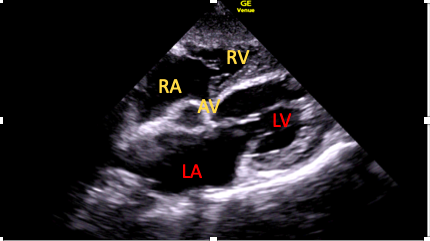

Subcostal Five-Chamber View

This is achieved by first optimizing the SC four-chamber view, followed by cephalic (anterior) tilting of the transducer. This will gradually bring the LV outflow tract (LVOT) and aortic valve into view (Figure 6). It may be possible to apply spectral Doppler here; however, poor alignment limits its utility. 15

Figure 6. The subcostal five-chamber view.

AV=aortic valve